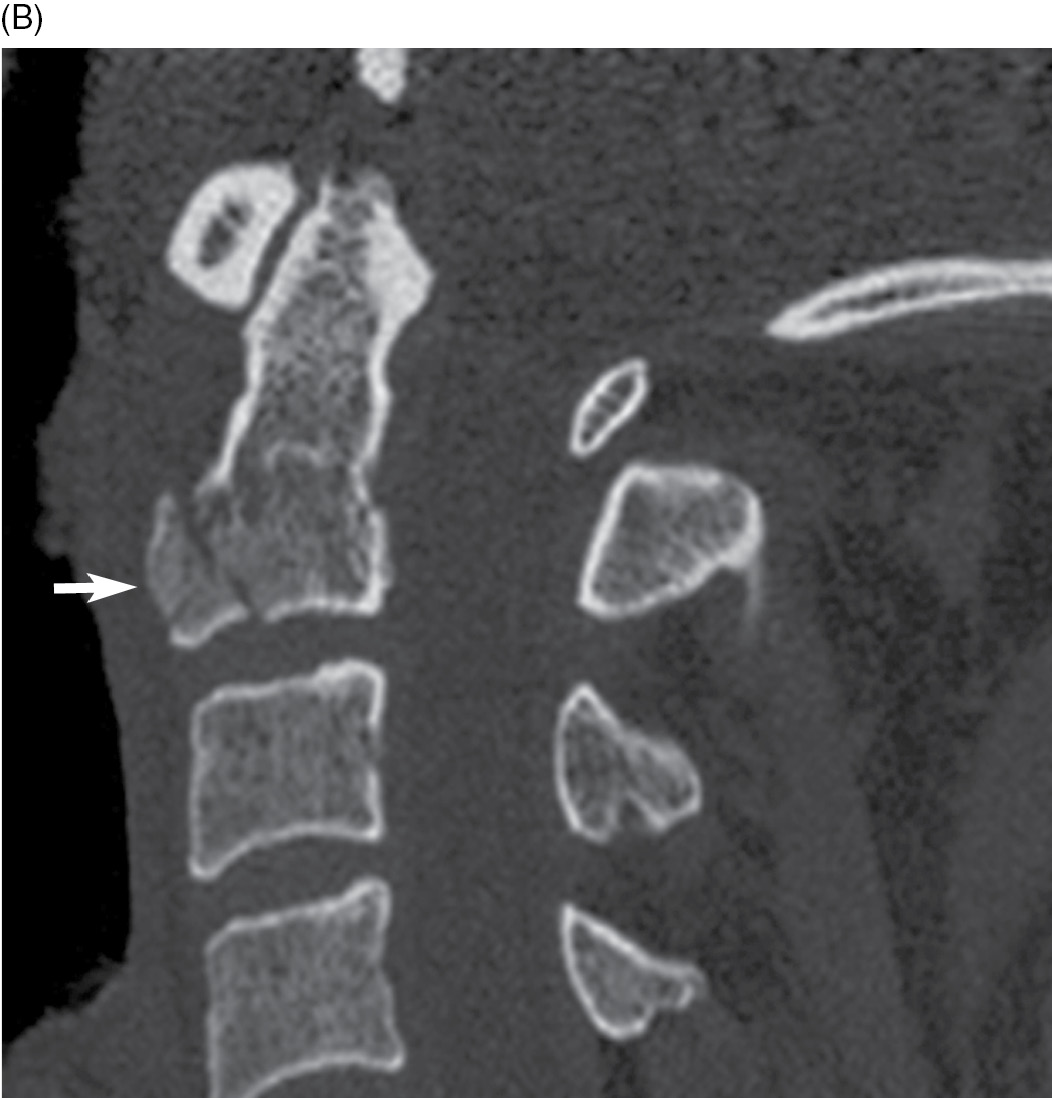

Don't Hang Around, It Could Be Incidental: A Case Report of Hangman's  Fracture and Review of the Literature, image size:1352x1576

Don't Hang Around, It Could Be Incidental: A Case Report of Hangman's Fracture and Review of the Literature